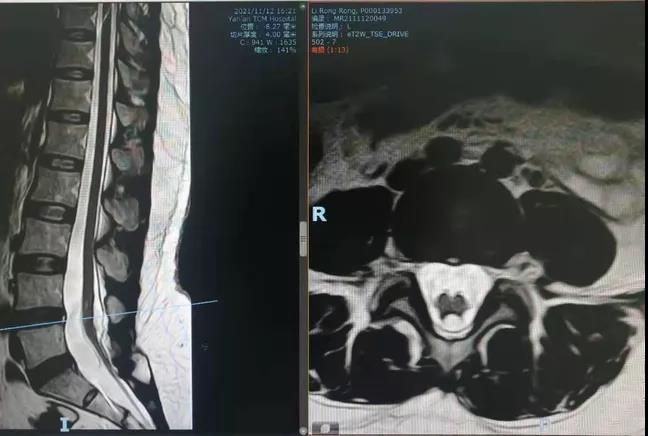

术前腰骶椎MR提示腰4-5平面椎管内脂肪样信号,圆锥位于腰5椎体平面。终丝增粗、紧绷。

术前术后对比:脂肪瘤明显缩小,终丝向上明显回缩